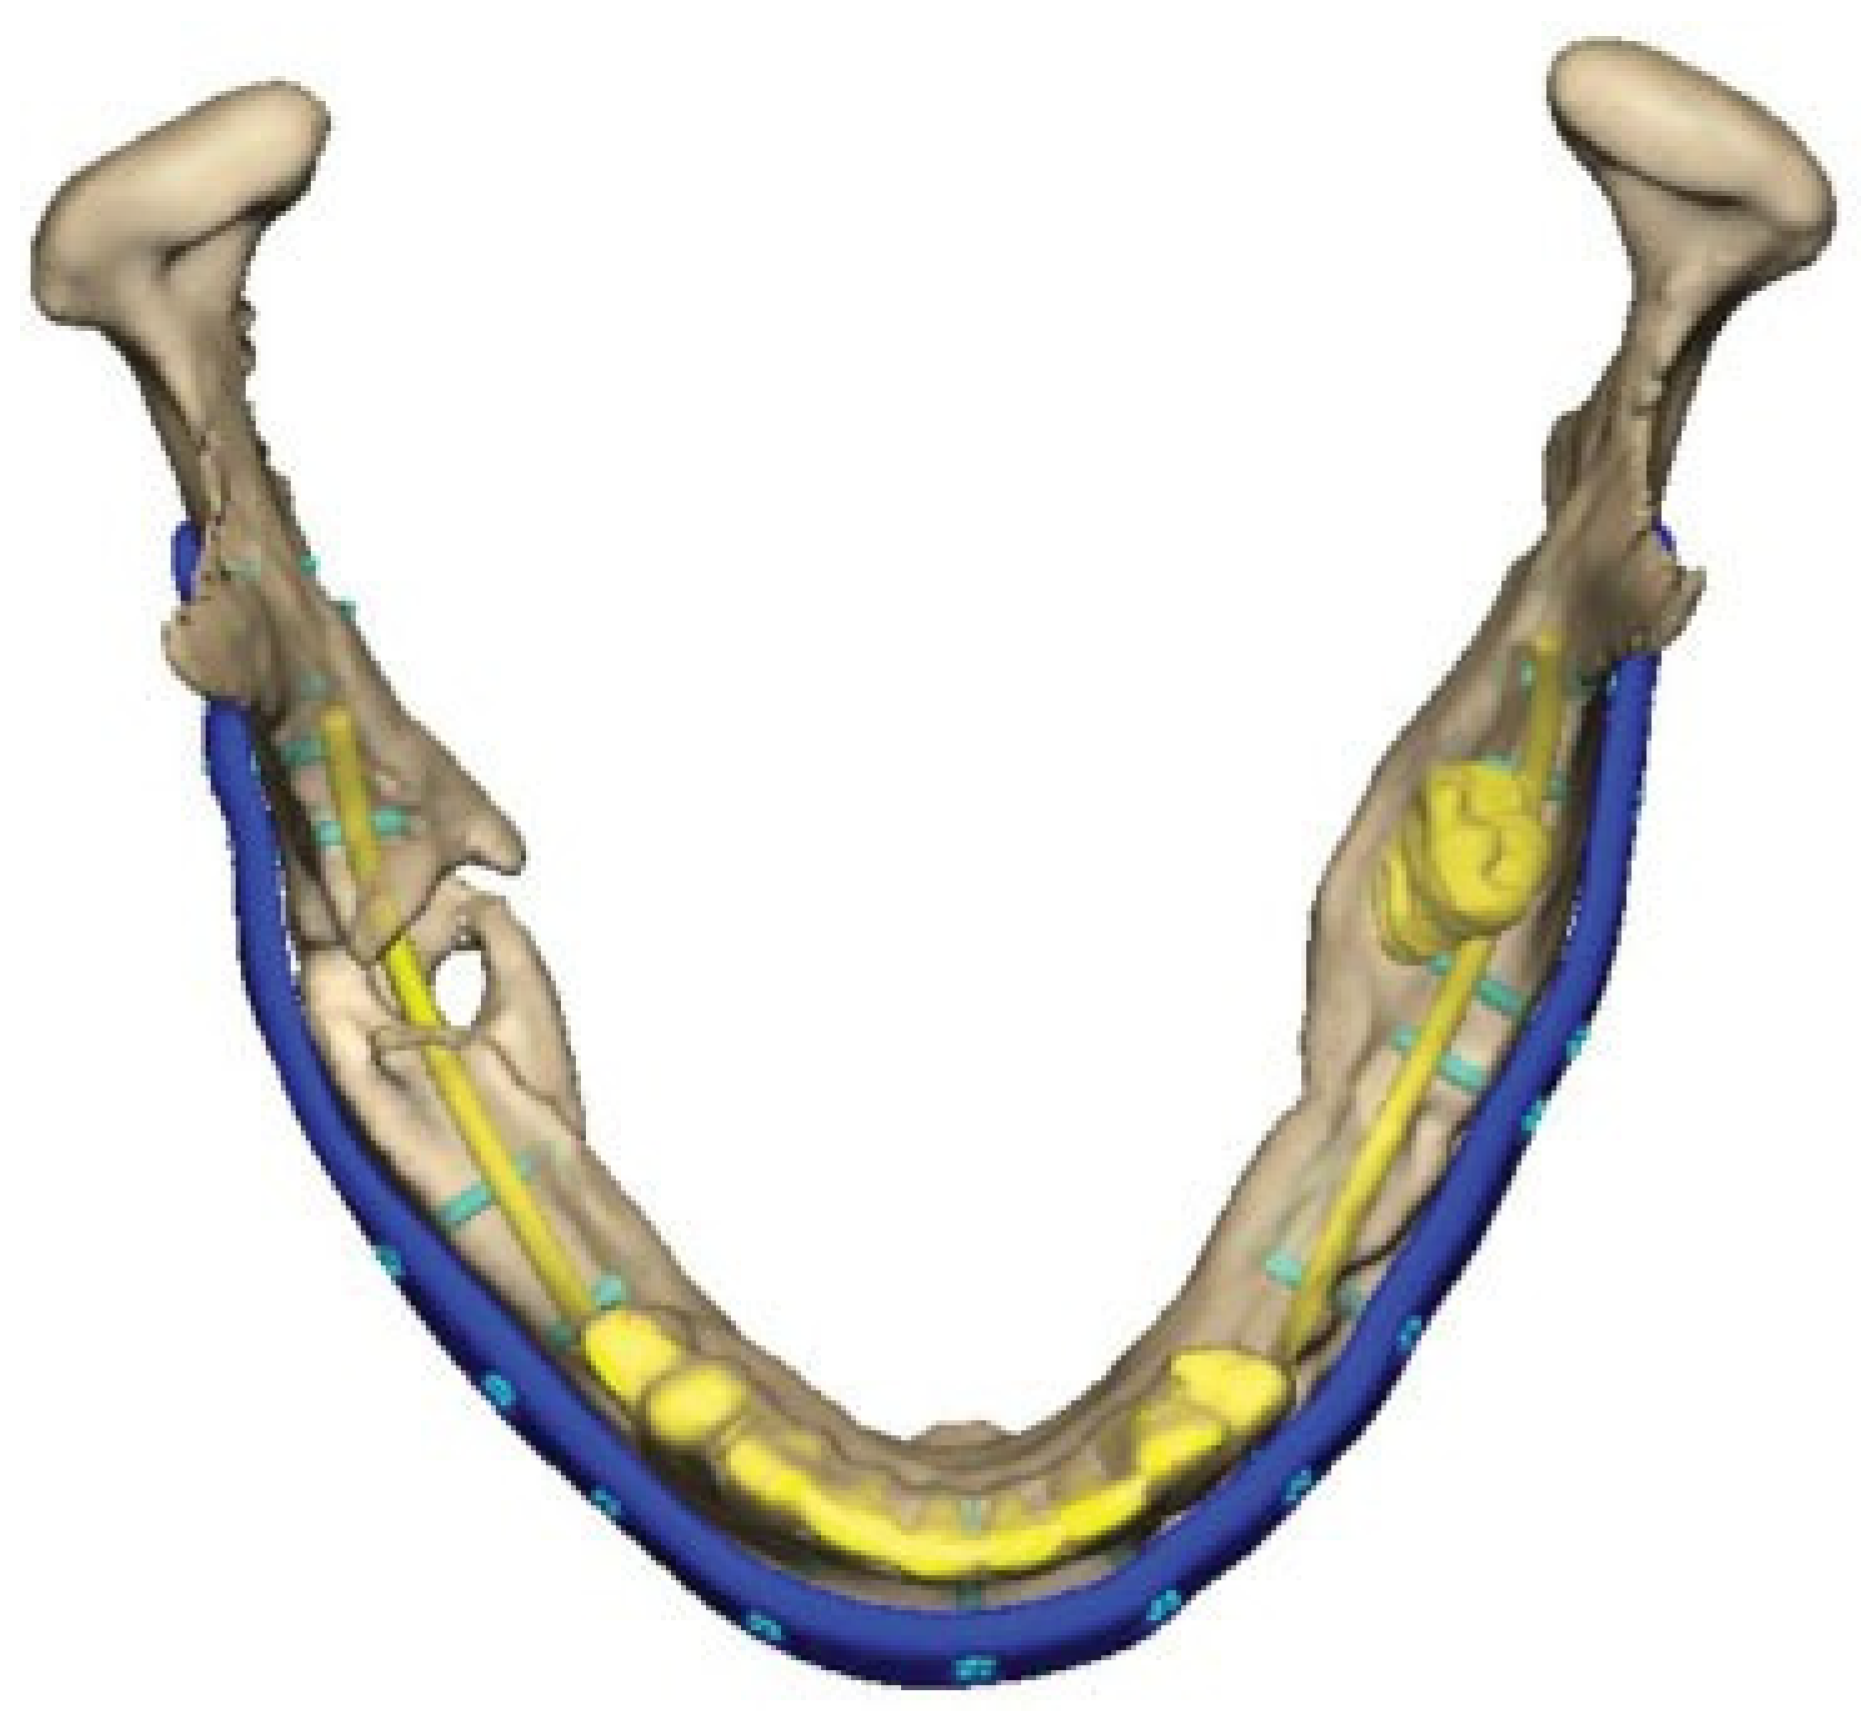

A Patient Specific Implant (PSI), an angle-to-angle mandibular reconstruction plate, was designed and outlined along the mandibular border. Plate holes with locking function for screws were outlined. The dimension of the plate was 2.5 mm thick and 8 mm wide. A total of 18 screw-holes were placed with care taken to avoid the fracture areas, teeth and nerves. (Figure 5) Simultaneously, a combined cutting- and drill guide was produced for osteotomies and drill holes virtually planned in the mandible. (Figure 6) The plate was then manufactured by milling from a titanium block (TRUMATCH® CMF, DePuy Synthes GmbH, Oberdorf, Switzerland) after the surgeon had approved its final form.

Figure 5.

Virtual design of plate and planning of holes and screw locations. Note the screws in the posterior left mandible avoiding the mandibular nerve and molar inside the bone.